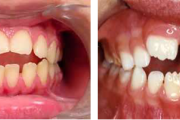

Turritavad ülemised lõikehambad.

Ruumipuudus eesmiste hammaste osas